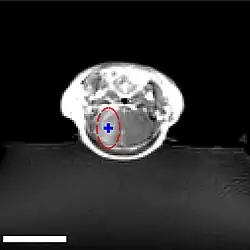

Über die Arteria carotis interna werden hyperosmolare Lösungen, beispielsweise von Mannitol oder Arabinose infundiert. Der unterschiedliche osmotische Druck zwischen den Endothelzellen und der infundierten Lösung bewirkt einen Flüssigkeitsverlust in den Endothelzellen, der zu deren Schrumpfung führt. Durch die Schrumpfung entstehen Zugkräfte zwischen den Zellen, was zu einer Öffnung der Tight Junctions und somit zur Öffnung der Blut-Hirn-Schranke führt.[127][128]

Aufgrund des Konzentrationsgradienten zwischen intravasalem und interstitiellem Raum fließt in größerer Menge Wasser aus dem Plasma ins Gehirn zurück (bulk flow). Dadurch werden im Wasser gelöste Moleküle in das Gehirn eingeschwemmt, wobei ein Ödem entsteht.[125][129][130][131][132]

Die durch die Schrumpfung der Endothelzellen bewirkte Öffnung der Tight Junctions beträgt etwa 20 nm.[132] Dadurch können Moleküle mit einem hydrodynamischem Durchmesser von ebenfalls etwa 20 nm in das Gehirn eindiffundieren.[133] Die Öffnung der Blut-Hirn-Schranke ist bei dieser Methode reversibel. Zehn Minuten bis spätestens zwei Stunden nach der Infundierung ist sie wieder vollständig hergestellt.[123][134] Die Einwirkungszeit der hyperosmolaren Lösung beträgt etwa 30 Sekunden. Durch eine Vorbehandlung mit einem Na+/Ca2+-Kanalblocker kann die Öffnungsdauer der Blut-Hirn-Schranke verlängert werden.

Das Verfahren wurde im Tiermodell mit einer Vielzahl von wasserlöslichen Wirkstoffen, Peptiden, Antikörpern, Enzymen und viralen Vektoren für die Gentherapie getestet. Eine Reihe von klinischen Studien zur Therapie von Gehirntumoren in Kombination mit Chemotherapeutika werden in verschiedenen Kliniken durchgeführt.[135] Die Ergebnisse sind für diese Anwendung vielversprechend.[136]